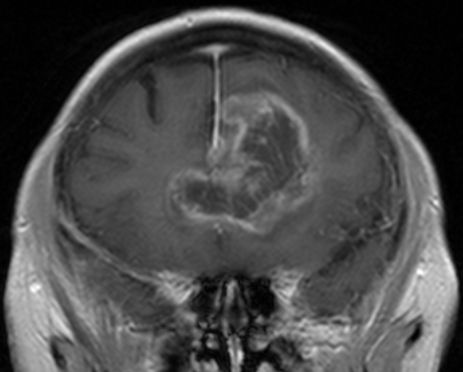

62-jähriger Mann mit torkeligem Gang, Amnesie und Verwirrtheit. Schmetterlingsgliom des hinteren Balkens.![]() |

Schmetterlingsgliom des hinteren Balkens |